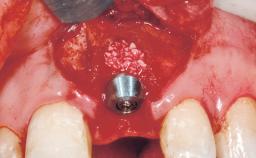

Late Placement of an Implant in a Maxillary Left Central Incisor Site

A 36-year-old female patient was referred for the replacement of the upper left central incisor (tooth 21), which had fractured. Although the tooth had been asymptomatic for many years, the crown began to loosen, at which time she presented to her dentist for an assessment. Teeth 21 and 22 had both been endodontically treated many years previously. She was a healthy individual and a non-smoker.

The crown of tooth 21 was splinted to the adjacent teeth with composite resin, and the gingiva was inflamed.